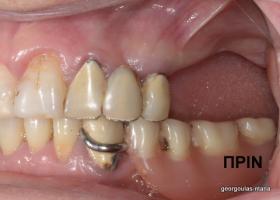

Η ασθενής αυτή είχε παλιές ακίνητες αποκαταστάσεις (γέφυρες) στην άνω γνάθο  κ μια κινητή προσθετική αποκατάσταση (μερική οδοντοστοιχία-"μασελάκι") στην κάτω γνάθο. Ήταν δυσαρεστημένη τόσο με την εμφάνιση όσο και με τη λειτουργία των δοντιών της καθώς παραπονιόταν ότι  είχαν εντονη κινητικότητα ενώ και οι προσθετικές τους εργασιές δεν ήταν σταθερές. Η πρόγνωση των δοντιών κρίθηκε φτωχή με αποτέλεσμα να μην είναι δυνατή η συμμετοχή τους σε μια νεα προσθετική αποκατάσταση με μακροχρόνια διάρκεια. Η ασθενής επιθυμούσε οι νέες αποκαταστάσεις να είναι σταθερές και ακίνητες.  Για το λόγο αυτό αποφασίστηκε η ολική αποκατάσταση της άνω κ κάτω γνάθου με ακίνητες επιεμφυτευματικές εργασίες. Στην αριστερή πλευρά της άνω γνάθου, λόγω μη επαρκούς οστού για την τοποθέτηση εμφυτευμάτων προηγήθηκε επέμβαση ανοιχτής  ανύψωσης ιγμορείου άντρου με τη χρήση πιεζοχειρουργικού μηχανήματος ώστε να δημιουργηθεί το κατάλληλο οστικό υπόστρωμα. Ακολούθησε σε επόμενο χειρουργείο η εξαγωγή των υπάρχοντων δοντιών κ η άμεση τοποθέτηση εμφυτεύματων (άμεση εμφύτευση) κ δύο μέρες μετά η τοποθέτηση προσωρινής εργασίας επί των εμφυτευμάτων (άμεση φόρτιση) με αποτέλεσμα η ασθενής να μη μείνει καθόλου χωρίς δόντια κ να είναι καλυμένη αισθητικά όσο καιρό διήρκησε η εργασία